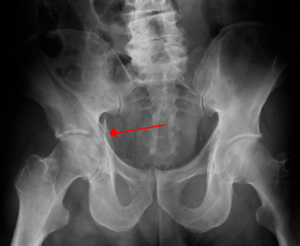

[[File:Acetabularfx.png|thumb|alt=Acetabular fracture (red arrow)|Right acetabular fracture (arrow)]] | |||

Radiographically

- Consider obtaining AP, Judet, and inlet/outlet films

- Iliopubic line extends from ilium to superior pubic ramus

- Ilioischial line- extends from ilium to ischial ramus forming radiographic teardrop, "U" shaped, on AP pelvis

- Quadrilateral plate forms medial wall of acetabulum